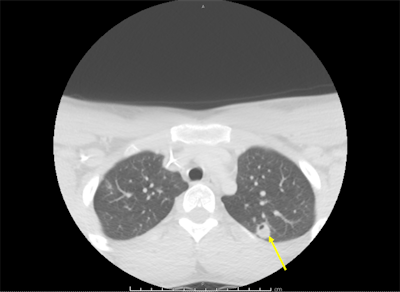

A neck ultrasound revealed a thrombosed superficial internal jugular vein consistent with thrombophlebitis, and a repeat chest x-ray showed right lung opacities indicating pneumonitis. A CT angiography (CTA) scan showed scattered nodular-appearing infiltrates throughout his lungs and moderate bilateral effusion. His blood tested positive for F. necrophorum.

Though the initial CTA failed to show pulmonary emboli, a subsequent CT scan showed evolving cavitation of the multiple nodular densities seen on the initial chest x-ray. The findings were consistent with septic pulmonary emboli. A vascular surgeon recommended that the teen's condition be managed without surgery.

The patient improved and was discharged after 12 days at the hospital. A CT scan was completed again at follow-up, which showed the jaw had a periosteal reaction. He was treated with six weeks of the antibiotic ertapenem. One month after discharge, imaging showed that the pulmonary infiltration and superficial internal jugular vein thrombosis had resolved, and the left mandibular osteomyelitis had improved.